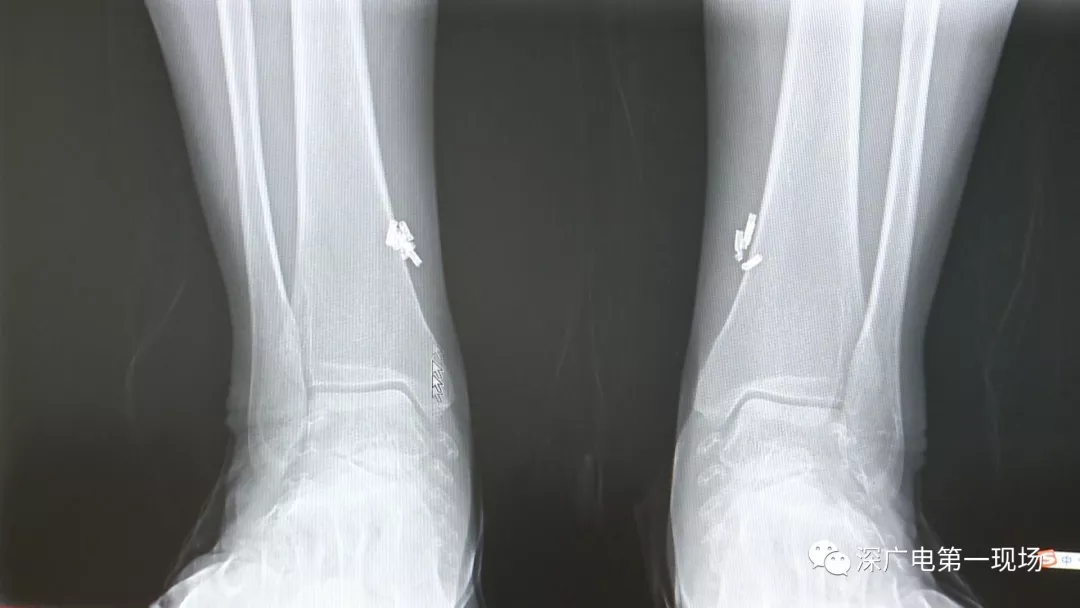

深圳一女子全身被植入彈簧圈,數(shù)量多到驚人!竟是為治這病…

出于保護(hù)患者,我們沒有直接采訪,但是通過醫(yī)生的介紹,記者了解到,病人是個(gè)36歲的女性,2歲開始就有癲癇病史,而且藥物治療也并不見效。

多方打聽之后,在山東某診所用全身埋彈簧圈的方式治療癲癇。陶主任介紹,這樣的方式想要治愈,那幾率也等同于撞大運(yùn)啊!

陶醫(yī)生介紹,目前并沒有看到一個(gè)特別正規(guī)的報(bào)道,說這種方法到底治了多少病人,總體的治愈率是多少,有多少病人能夠發(fā)作減輕,這個(gè)是沒有看到。